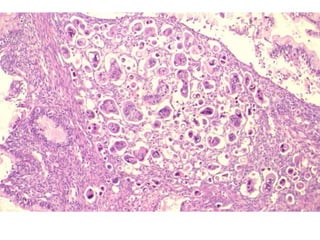

Hiperplasia complexa com atipias / Neoplasia intraepitelial endometrial (EIN)